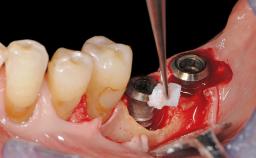

Treatment of Peri-Implant Mucositis at a Zirconia Implant